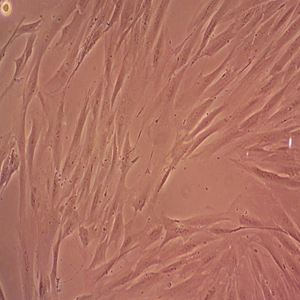

细胞形态:

上皮样

生长状态:

贴壁